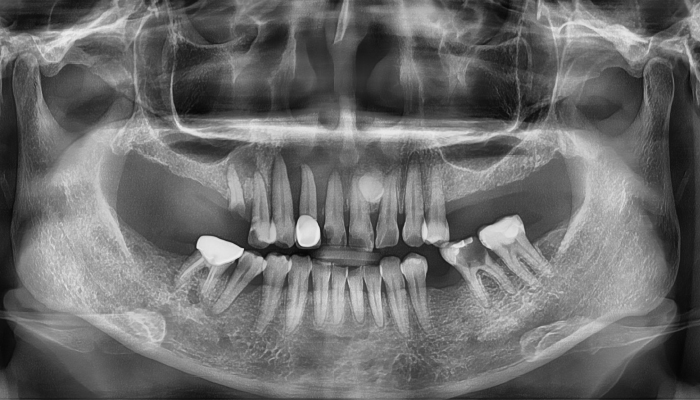

• 식립전

식립후